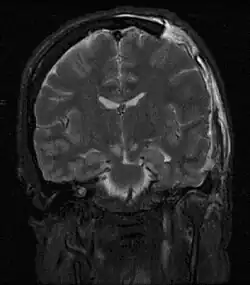

| MRI showing injury due to brain herniation | |

Brain herniation is a potentially deadly side effect of very high pressure within the skull that occurs when a part of the brain is squeezed across structures within the skull. The brain can shift across such structures as the falx cerebri, the tentorium cerebelli, and even through the foramen magnum (the hole in the base of the skull through which the spinal cord connects with the brain). Herniation can be caused by a number of factors that cause a mass effect and increase intracranial pressure (ICP): these include traumatic brain injury, intracranial hemorrhage, or brain tumor.[1]